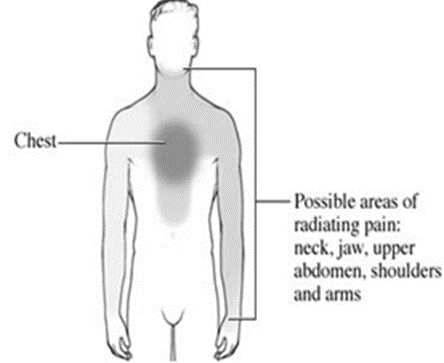

Symptoms of myocardial infarction

• Severe chest pain

• Sweating

• Chest pain radiating through jaw, shoulder, arms and back

• Epigastric discomfort with or without nausea/ vomiting

• Sproathy and blood stained sputum

• Dizziness, weakness, Anxiety

• Irregular heart beat

• Heart burn & indigestion